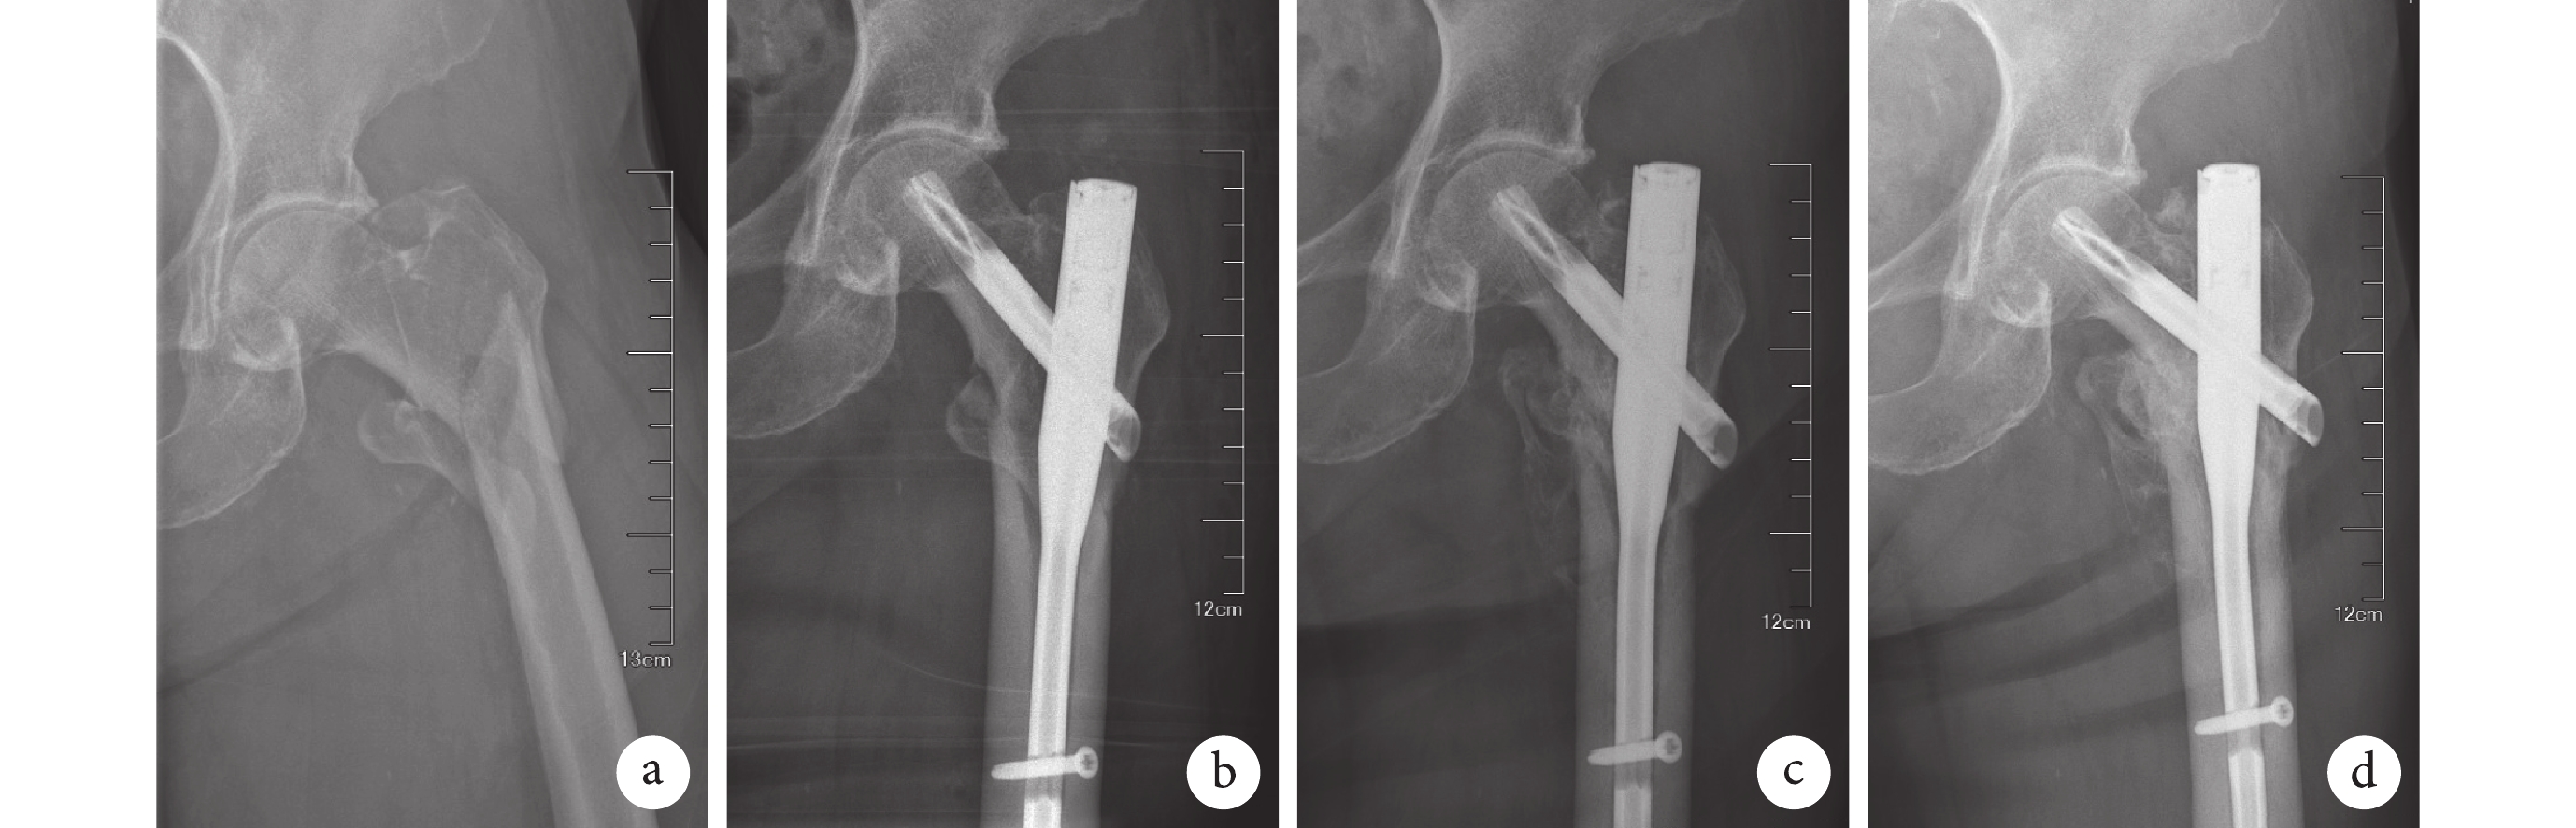

a. 術前;b. APFN 內固定術后即刻復位滿意,TAD<25 mm、Cal-TAD>25 mm;c. 術后 3 個月骨痂形成,力線良好;d. 術后 1 年骨折愈合,力線發生改變,股骨頸內翻塌陷

Figure1. X-ray films of a 85-year-old female patient with left femoral intertrochanteric fracture (type A3)a. Before operation; b. The fracture reduction was satisfactory with the TAD<25 mm and Cal-TAD>25 mm at immediate after operation; c. The callus formed and the line of force was good at 3 months after operation; d. The fracture healed, but the line of force changed, and the femoral neck was collapsed at 1 year after operation

TAD<25 mm 與≥25 mm 組間并發癥發生率比較,差異有統計學意義(χ2=5.010,P=0.025)。見表 1。其中,TAD<25 mm 患者發生骨折延遲愈合或不愈合 1 例、螺旋刀片軸向移動 1 例、股骨頸內翻塌陷或螺旋刀片向上切出 4 例;TAD≥25 mm 患者發生骨折延遲愈合或不愈合 1 例、螺旋刀片軸向移動 3 例、股骨頸內翻塌陷或螺旋刀片向上切出 5 例、內固定物松動或斷裂 1 例。見圖 1、2。